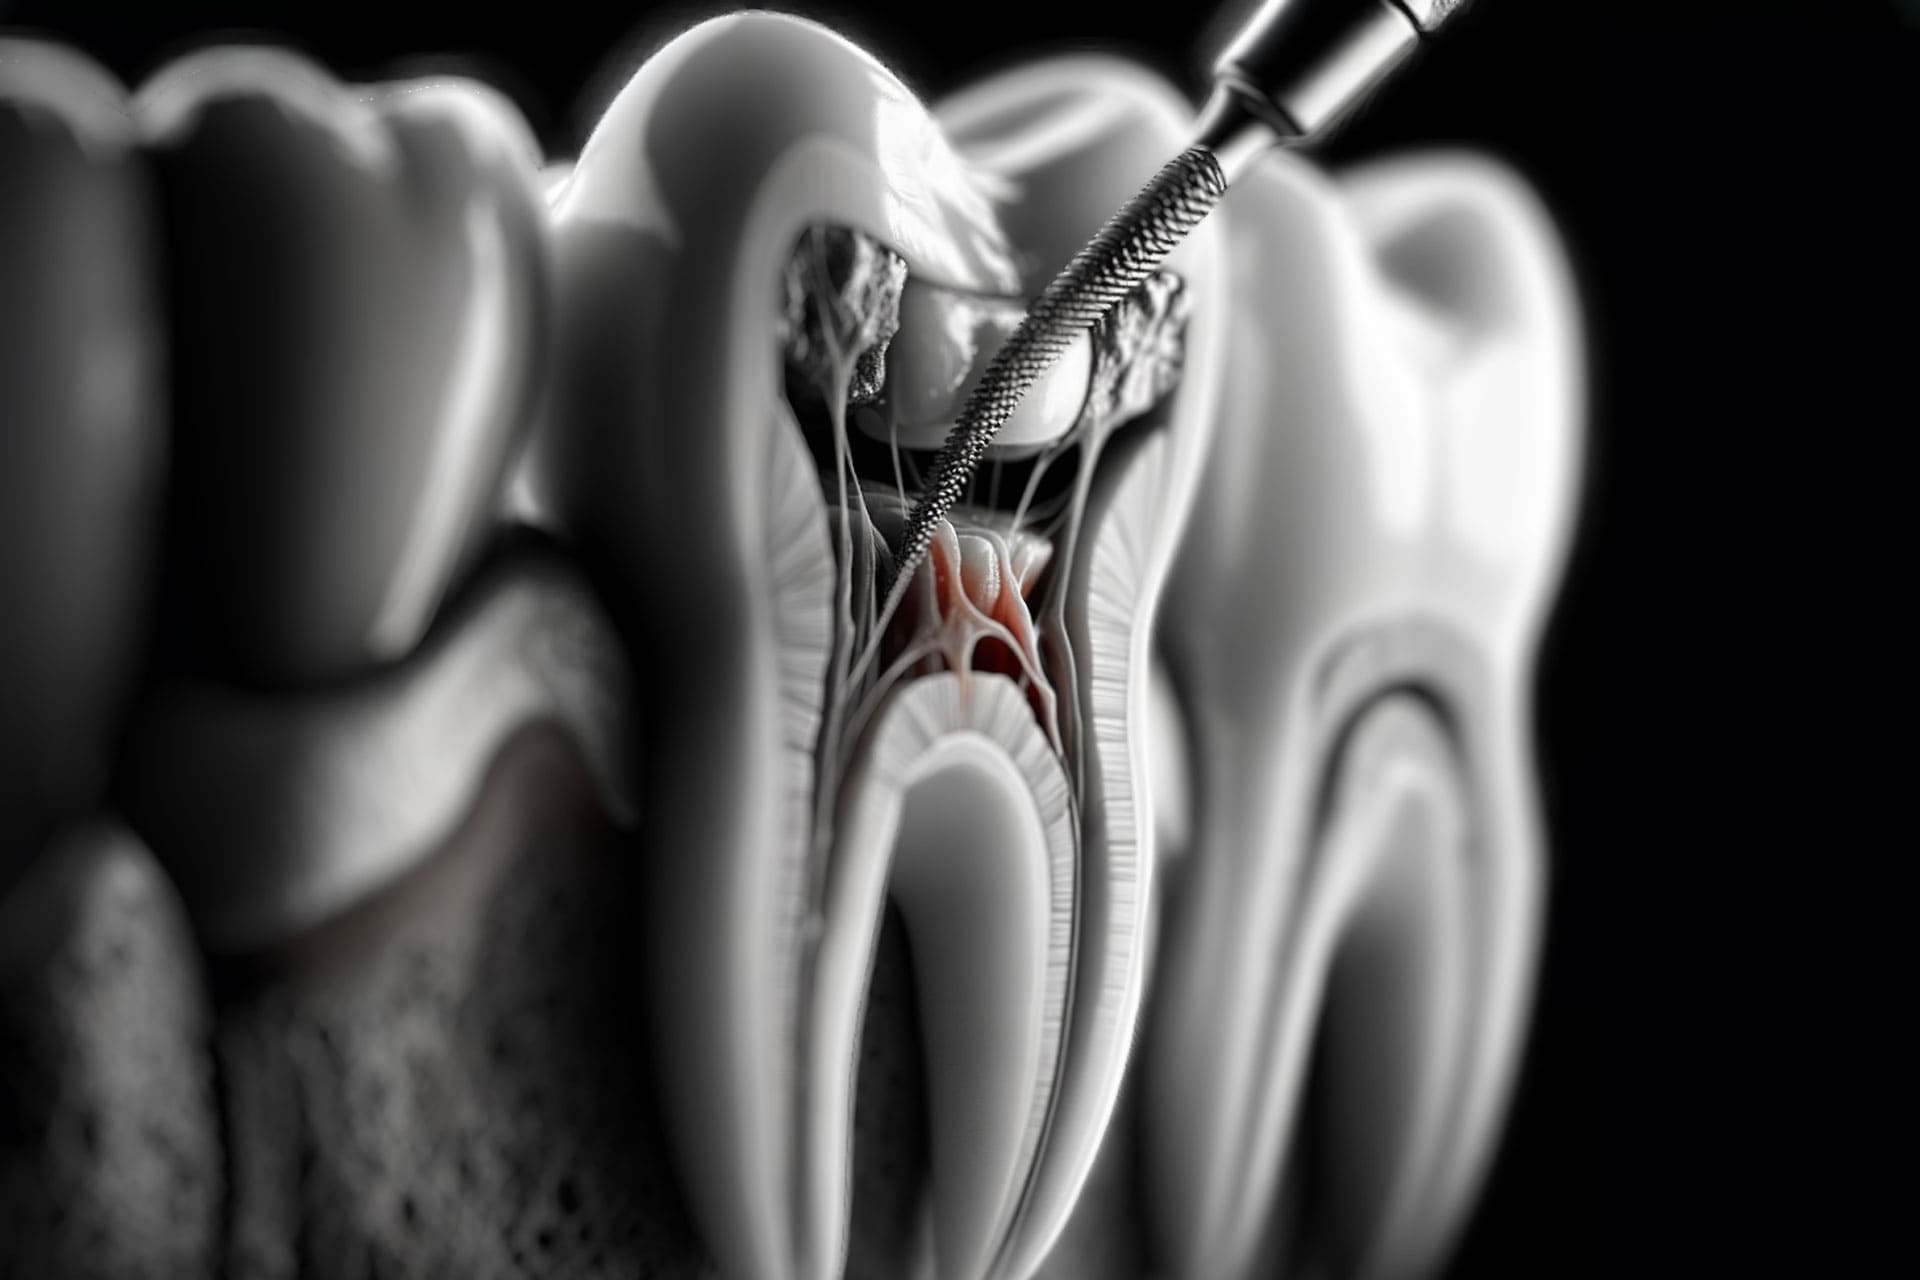

Diş kanalları, pulpada başlayan ve kök kısmına doğru inen kanallardır. Kanal tedavisi de bu kanalların temizlenmesi esasına dayanılarak yapılır. Kök kanalları olarak da adlandırılan bu yapılar pulpada yer alır. Diş minesi ve dentinde meydana gelen bir hasar pulpanın ve kök kanallarının enfekte olmasına, iltihaplanmasına, derin çürümeye bağlı hasar almasına hatta pulpanın nekzoruna yani ölmesine neden olur.

anal tedavisi iltihaplanan, enfekte olan kök kanalındaki bakterileri yok etmek ve dişin yeniden enfeksiyon yapmasını engellemek, doğal dişi korumak için yapılan bir tedavi yöntemidir. Kanal tedavisinde süreç kök kanalına girilmesi, enfekte olan pulpanın çıkarılması ve dişin iç kısmının dikkatlice temizlenip dezenfekte edilmesi işlemleri ile ilerler. Son olarak diş doldurulur ve yeniden enfekte olmaması için mühürlenir.

Kanal tedavisinde başarı elde etmek için uygulamanın eksiksiz bir şekilde yapılması esastır. Uygulamada başarı oranının artabilmesi için özellikle kök kanalı şekillendirmesinde ortaya çıkabilecek sorunların elenmesi gerekir. Kök kanalına müdahale ederken kullanılan döner alet ve rotary sistemler sayesinde günümüzde kanal tedavisinden yüksek başarı oranlarına ulaşmak mümkün olmaktadır.

Bunun yanı sıra apex locater olarak adlandırılan ve kanal tedavisinde kanal içi operasyonun uzunluğunu ölçmek için kullanılan cihazlar kök ucunun en dar noktasına ulaşmaya yardımcı olur. Bu sayede hem tedavi süresinde kısalma elde edilir hem de kök ucunun en dar noktasına ulaşarak tedavinin daha etkili olması sağlanır.

Tedavide diş etlerine lokal anestezi yapılır. Bölgede yeterli uyuşma sağlandığında dişin üst kısmından ufak bir delik açılır. Enfekte olan, iltihaplanan ve derin çürümeye bağlı hasar alan pulpa bu delikten çıkarılır. Diş içerisindeki kök kanallarının detaylı bir şekilde temizlenmesi de önemlidir. Kanallar temizlendikten ve dezenfekte edildikten sonra diş geçici dolgu ile kapatılır.